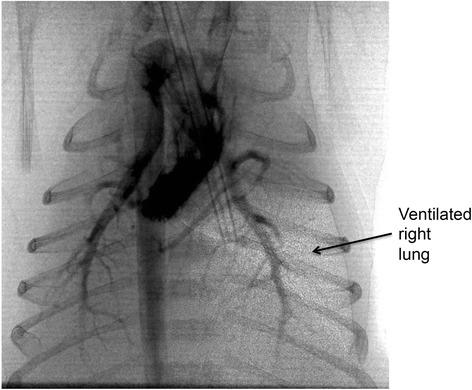

While it is now recognized that umbilical cord clamping (UCC) at birth is not necessarily an innocuous act, there is still much confusion concerning the potential benefits and harms of this common procedure. It is most commonly assumed that delaying UCC will automatically result in a time-dependent net placental-to-infant blood transfusion, irrespective of the infant's physiological state. Whether or not this occurs, will likely depend on the infant's physiological state and not on the amount of time that has elapsed between birth and umbilical cord clamping (UCC). However, we believe that this is an overly simplistic view of what can occur during delayed UCC and ignores the benefits associated with maintaining the infant's venous return and cardiac output during transition. Recent experimental evidence and observations in humans have provided compelling evidence to demonstrate that time is not a major factor influencing placental-to-infant blood transfusion after birth. Indeed, there are many factors that influence blood flow in the umbilical vessels after birth, which depending on the dominating factors could potentially result in infant-to-placental blood transfusion. The most dominant factors that influence umbilical artery and venous blood flows after birth are lung aeration, spontaneous inspirations, crying and uterine contractions. It is still not entirely clear whether gravity differentially alters umbilical artery and venous flows, although the available data suggests that its influence, if present, is minimal. While there is much support for delaying UCC at birth, much of the debate has focused on a time-based approach, which we believe is misguided. While a time-based approach is much easier and convenient for the caregiver, ignoring the infant's physiology during delayed UCC can potentially be counter-productive for the infant.